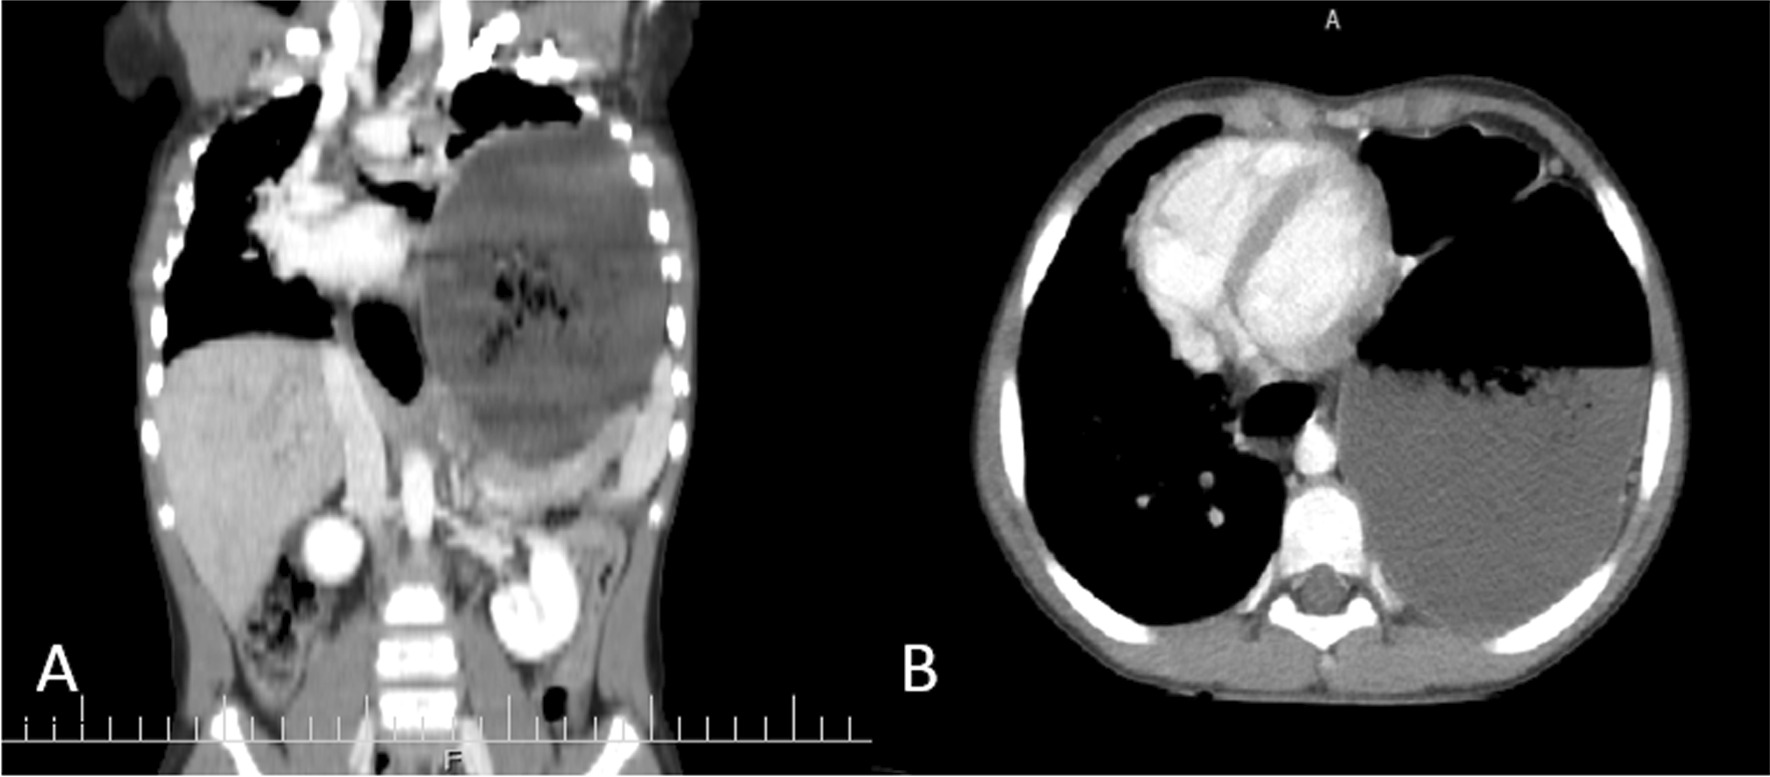

On spiral computed tomography (CT) scan of the lung with intravenous contrast, shifting of the heart and mediastinum to the right side due to pressure effect of a dilated stomach and colon was reported. Colon loop occupying most of the left hemithorax was seen. The esophagus at the distal third was dilated, too, which suggests esophageal hiatal hernia and gastric volvulus (Fig. 3).

Fig. 3.

Abdominal CT scan (coronal, A; axial, B) revealing mild free fluid at the abdominopelvic cavity. Dilated stomach and colon loop are at the left hemithorax